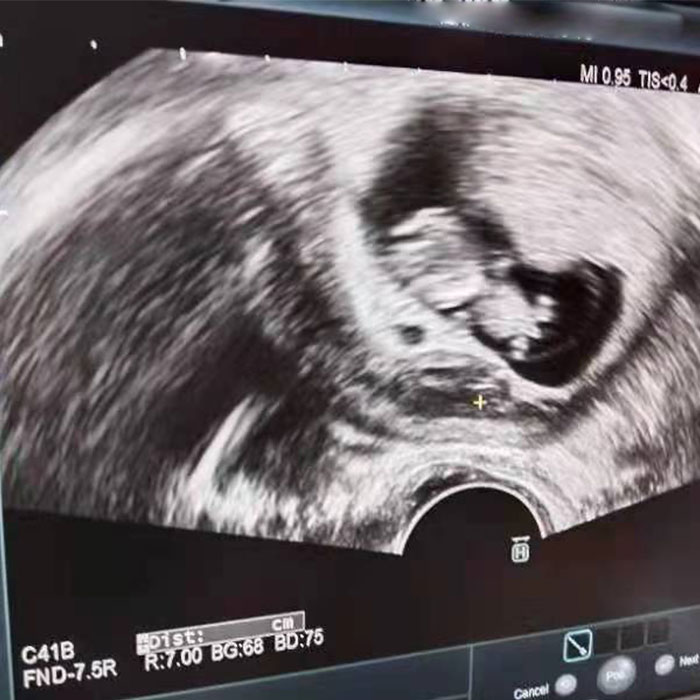

輸卵管問題+不完全縱膈子宮,泰國三代試管嬰兒助孕竟一次成功!

楊女士與田先生結(jié)婚多年,早年因忙于事業(yè)無心生育,近年來想要生孩子了,卻遲遲備孕不成。去醫(yī)院檢查才發(fā)現(xiàn)右側(cè)輸卵管堵塞,左側(cè)欠佳,子宮情況有些不太理想,是不完全縱膈子宮。后經(jīng)朋友介紹,了解到泰國DHC生殖醫(yī)院,經(jīng)考察選擇赴泰做試管,并成功懷上小王子!

后面去醫(yī)院檢查,才發(fā)現(xiàn)右側(cè)輸卵管堵塞,左側(cè)欠佳,子宮情況有些不太理想,是不完全縱膈子宮。在多個醫(yī)院治療后,還是未能自然受孕。

針對楊女士夫妻的情況,萬星博士與周志杰主任在聯(lián)合視頻問診下,為其制定了個性化試管嬰兒方案。經(jīng)過一段時間助孕寶調(diào)理后,楊女士啟動了赴泰試管計劃。在萬星博士及其他醫(yī)護團隊的共同守護之下,楊女士的試管嬰兒過程十分順利,AMH1.8,基礎卵泡8個的楊女士最終獲得8顆成熟卵子,成功受精8顆,獲得5天囊胚6個。對于這樣的結(jié)果,楊女士非常開心。

為了更好地提高試管嬰兒成功率,在移植前,萬星博士為楊女士進行“宮腹腔鏡微創(chuàng)手術”:一方面借助腹腔鏡處理盆腔輸卵管病變,明確診斷處理盆腔內(nèi)影響生育的因素;另一方面,也可以通過宮腔鏡實施“子宮不完全縱隔分離術”,從而改善妊娠結(jié)局。

最終,楊女士移植了一枚男胚一次成功懷孕!

子宮(不全)縱隔是子宮先天發(fā)育過程中,雙副中腎管融合受阻、腔化不全的表現(xiàn),通過彩超或造影可以觀察到,確診則主要依靠宮腔鏡。